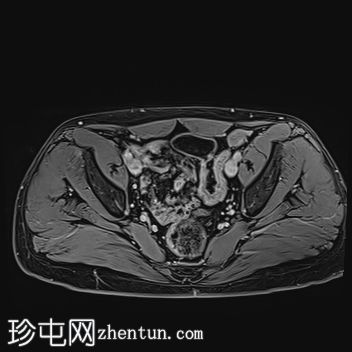

MRI

左侧阴囊空虚。

左侧睾丸位于盆腔左侧前壁,腹股沟管上方。其体积较小(与对侧正常的右侧睾丸相比)。T2加权像呈高信号,T1加权像呈低信号,未见明显局灶

性病

变。

右侧睾丸位于右侧阴囊内,大小和形状正常。